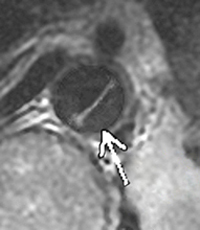

На следующий день, после того, как верующие помолились за неё, врачи провели ещё одну компьютерную томографию, чтобы точно определить местоположение трещины перед операцией. На этот раз снимки показали абсолютно здоровое сердце. Весьма озадаченный, хирург сказал миссис Гриффин: “Я не знаю, что вам сказать. У вас было расслоение аорты, но теперь от этого не осталось и следа”. Он показал ей снимки сделанные до и после молитвы. “Вы можете идти. И между прочим, у вас также нет никакого рака. Вы абсолютно здоровы”.

Стрелка, нанесённая врачом, указывает на аорту, которая представляет собой темную, круглую областью в центре изображения. Диагональная линия – это аневризм или расслоение аорты, которая нуждается в срочной операции и может оказаться фатальной в случае разрыва. На следующий день был осуществлено второе сканирование сердца. Расслоение полностью исчезло и никогда больше не возникало.